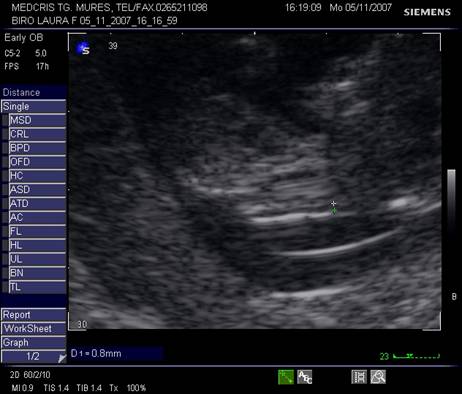

Fig. nr.129 Masurarea pliului nuchal la o marire corespunzatoare

Fig. nr.130 Os nazal evident la o sarcina de 12 saptamani ( sageata)

Masurarea NT egala sau peste 3 mm este considerata anormala. Riscul defectelor cromozomiale creste marcat in functie de marimea NT si de varsta mamei, necesitand punctie biopsie de vilozitati choriale sau amniocenteza.